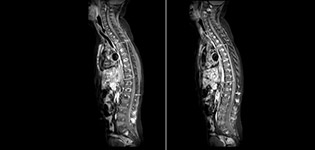

Routinely obtaining homogeneous fat suppression under virtually all conditions with mDIXON TSE

Philips mDIXON TSE is a two-point DIXON technique that separates water and fat signals, for time-efficient fat-free imaging, even in challenging neuro anatomy.

“mDIXON TSE has been one of the most significant improvements in imaging sequences that we have utilized to date at PCH,” says Dr. Miller. “Its multi-parametric acquisition allows us to obtain fat suppressed images and equivalent non-fat suppressed T2 images all in the same sequence. In addition, prior methods of fat suppression could be artifactually corrupted by poor patient anatomy or poor operator application, but with mDIXON we now have a robust and reliable method of fat suppression.”

Fat saturation is historically challenging at the ends of fields of view, especially in total spine imaging and in difficult patient anatomy such as the lower regions of the neck. “Due to the unique fat suppression capabilities of mDIXON, however, these challenges no long apply,” says Dr. Miller. “We routinely obtain homogeneous fat suppression under virtually all conditions. It has also led to some efficiencies by not having to repeat sequences because of that technical failure.”

mDIXON TSE makes a difference

“mDIXON TSE is most useful in patients with lesions or abnormalities in the soft tissues such as the face and neck, and for patients with contrast enhancing abnormalities that are mostly visible with fat suppression,” says Dr. Miller. “All our spine imaging now routinely contains mDIXON water-only T2 images, and this allows us to identify pathology that may be obscured by non-fat suppressed imaging such as injuries of the bone. And it’s not necessary to obtain additional standard TSE T2 images because the in-phase mDIXON images are equivalent to standard TSE T2 images.”

“mDIXON TSE has increased our diagnostic confidence in ruling in or ruling out abnormalities in which fat suppression is critical to diagnosis, such as metastatic disease or osseous abnormalities.”